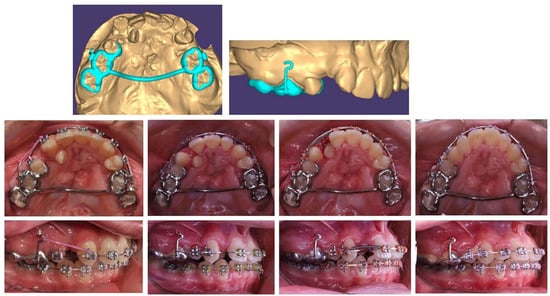

Based on the patient’s digital model, a lingual arch design was made with a hook in suitable location and direction to ensure the desired tooth movement of the lower-right lateral incisor (Figure 2). The body of the PDaA was maximally reduced, but at the same time, it was stable enough to be an anchorage. The patient adapted to it in a short period of time, and the biomechanical system used showed a good result.

Figure 2. Treatment progress in insertion of a lower-right lateral in the dental arch, using a lingual arch support.